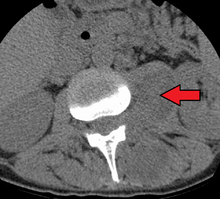

An abscess in the psoas muscle of the abdomen may be caused by lumbar tuberculosis. Owing to the proximal attachments of the iliopsoas, such an abscess may drain inferiorly into the upper medial thigh and present as a swelling in the region.

Paraspinal abscess in the psoas muscle